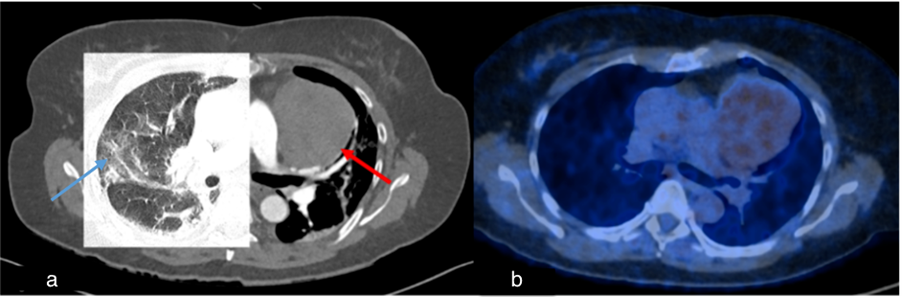

Figure 7.

Case 4, 66-year-old male with history of marginal zone lymphoma. A chest CT scan was performed after recovering from COVID-19 to assess post-primary changes in the lung. No pathological lung findings were observed. However, an incidental finding of a short dissection in the superior mesenteric artery was noted (red arrow). Additionally, the spleen (blue asterisk) and retroperitoneal lymph nodes (small yellow asterisk) are enlarged, consistent with the underlying disease.